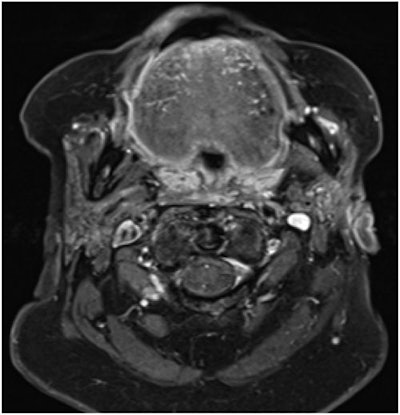

Due to the observed facial nerve palsy and bone destruction, clinicians suspected malignancy of the parotid gland. The team ordered a magnetic resonance imaging (MRI) scan, which showed a large necrotic mass of 5.8 x 4.8 x 7.3 cm extending from the superficial lobe of the woman's left parotid gland to her external ear canal, cutis, temporomandibular joint, and lower neck, confirming she had a parotid abscess, according to the report.